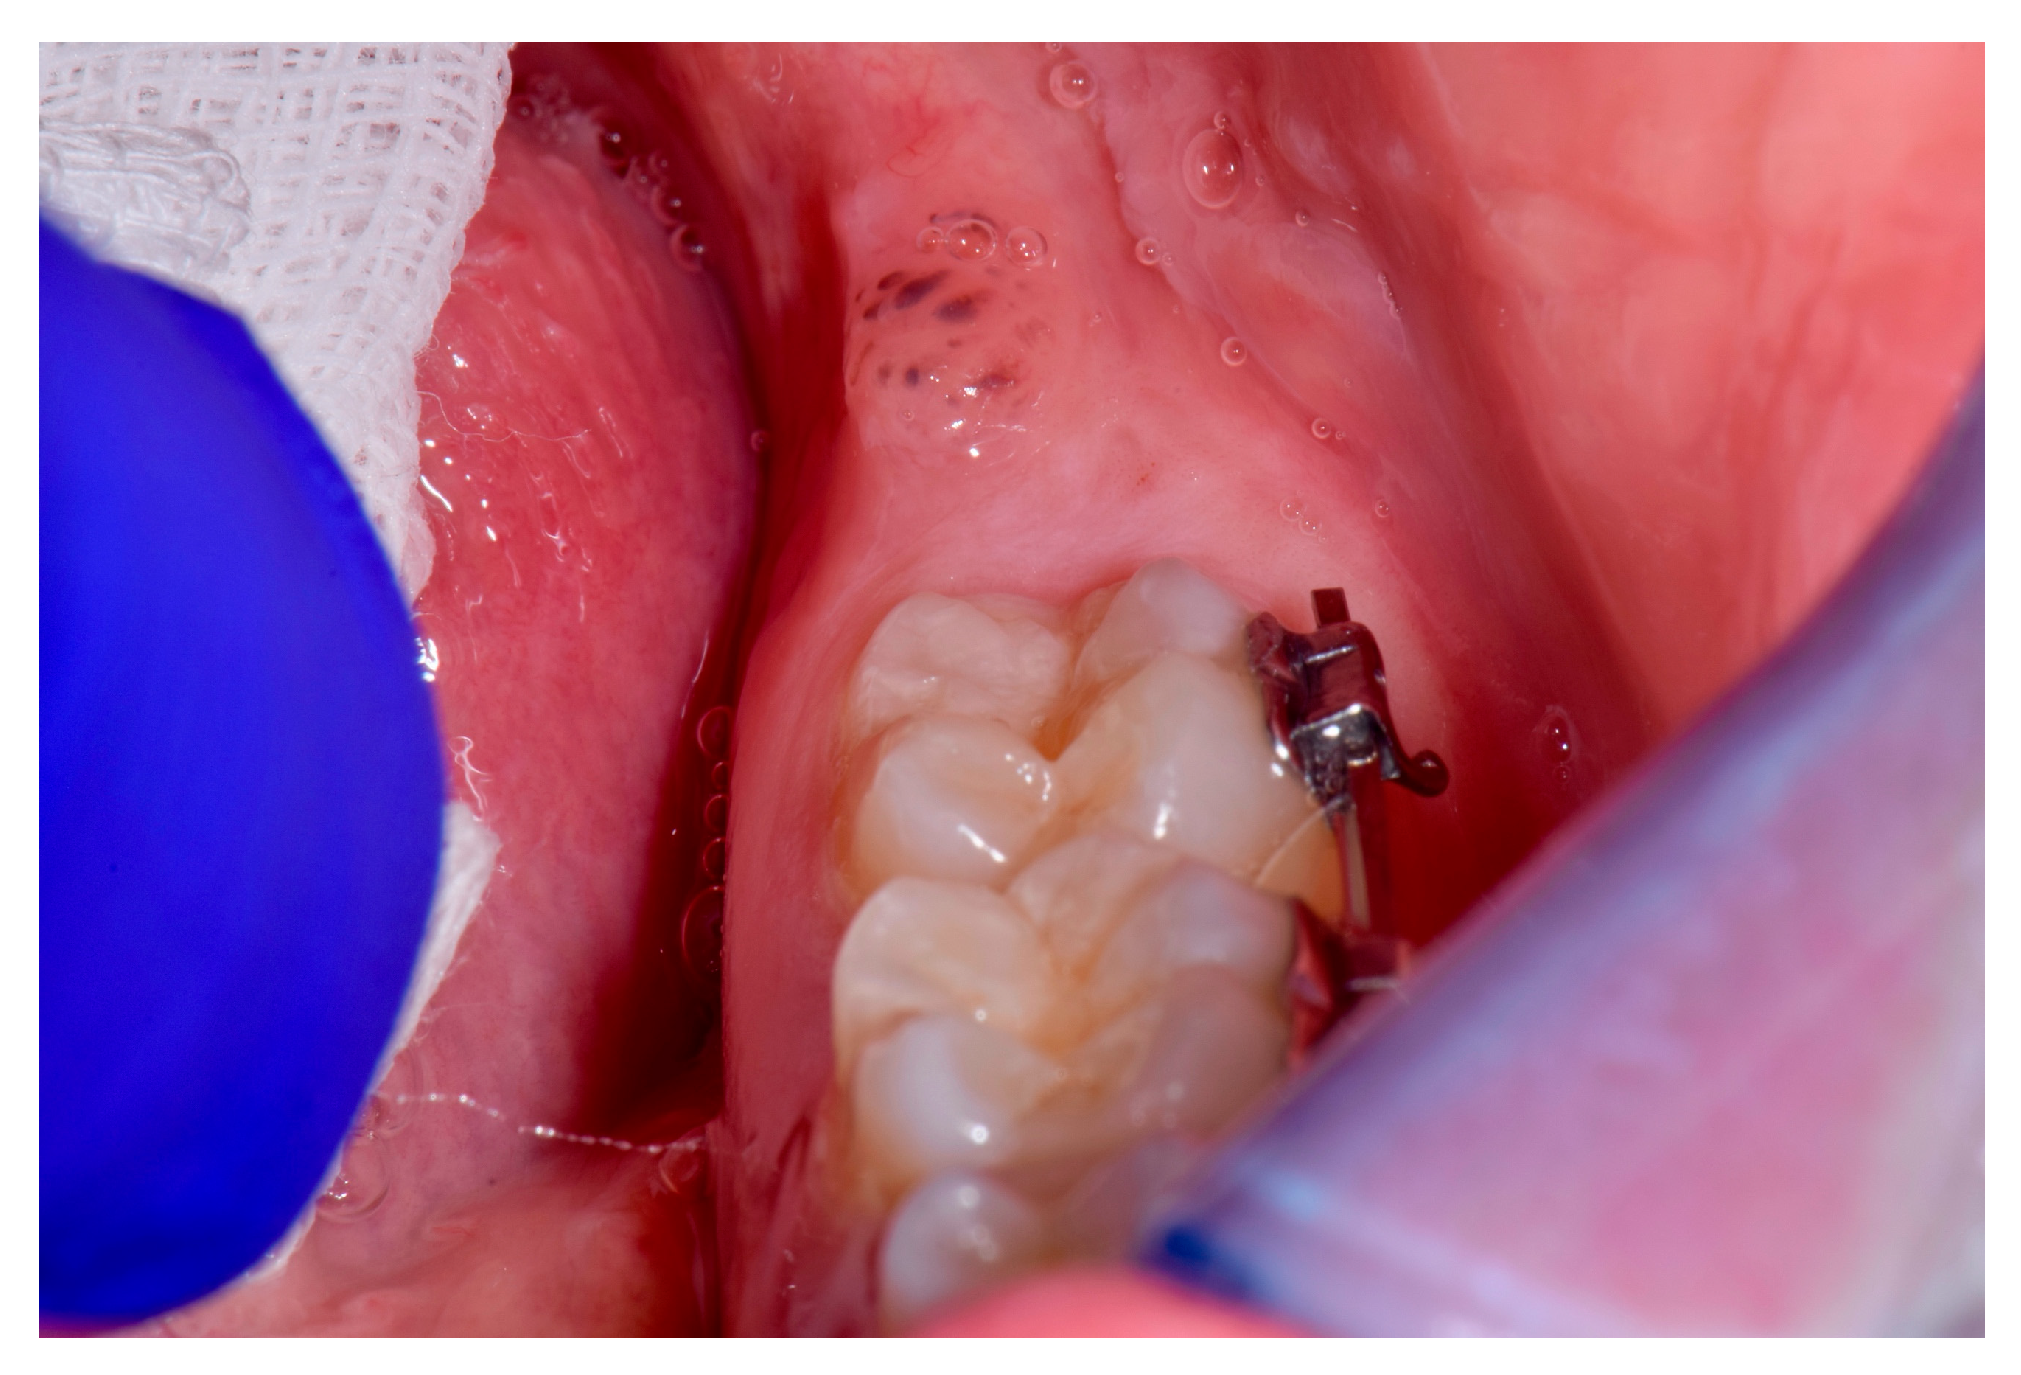

Nevus in the Oral Cavity †

2. Case

3. Treatment